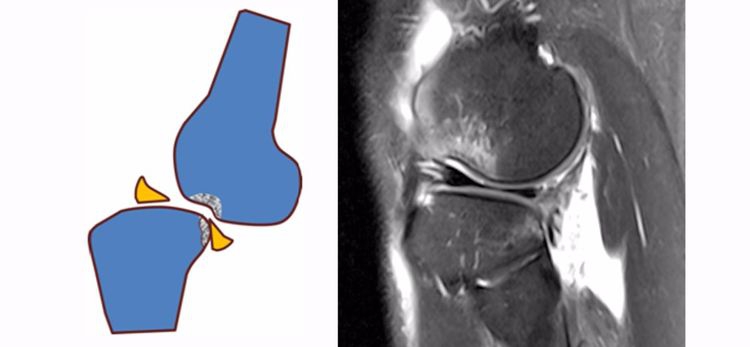

2.方向异常(ACL 下垂征):有较完整的韧带低信号,但方向异常,呈下垂状。一般见于股骨附着部的陈旧损伤,损伤的ACL下垂并粘附在PCL上。

3.ACL 消失:髁间窝空虚,无韧带信号。见于较久的损伤,损伤的ACL撕裂较重呈马尾状,无滑膜包裹,逐渐被关节内的酶腐蚀而消失。

5.假瘤:韧带损伤后断端较整齐,残端组织增生并被滑膜包裹呈"瘤状",如果突出于前方为"独眼征",多见于韧带股骨附着部撕裂及部分撕裂。

6.扭曲和空虚:髁间窝内似隐隐约约有低信号,边缘明显,中央空虚;或者中央有低信号,但扭曲如麻花状。多为陈旧损伤,仅存ACL的滑膜,里面可有少量的韧带纤维,粘附在后方,随着膝关节的长时间屈伸逐渐呈扭曲状。